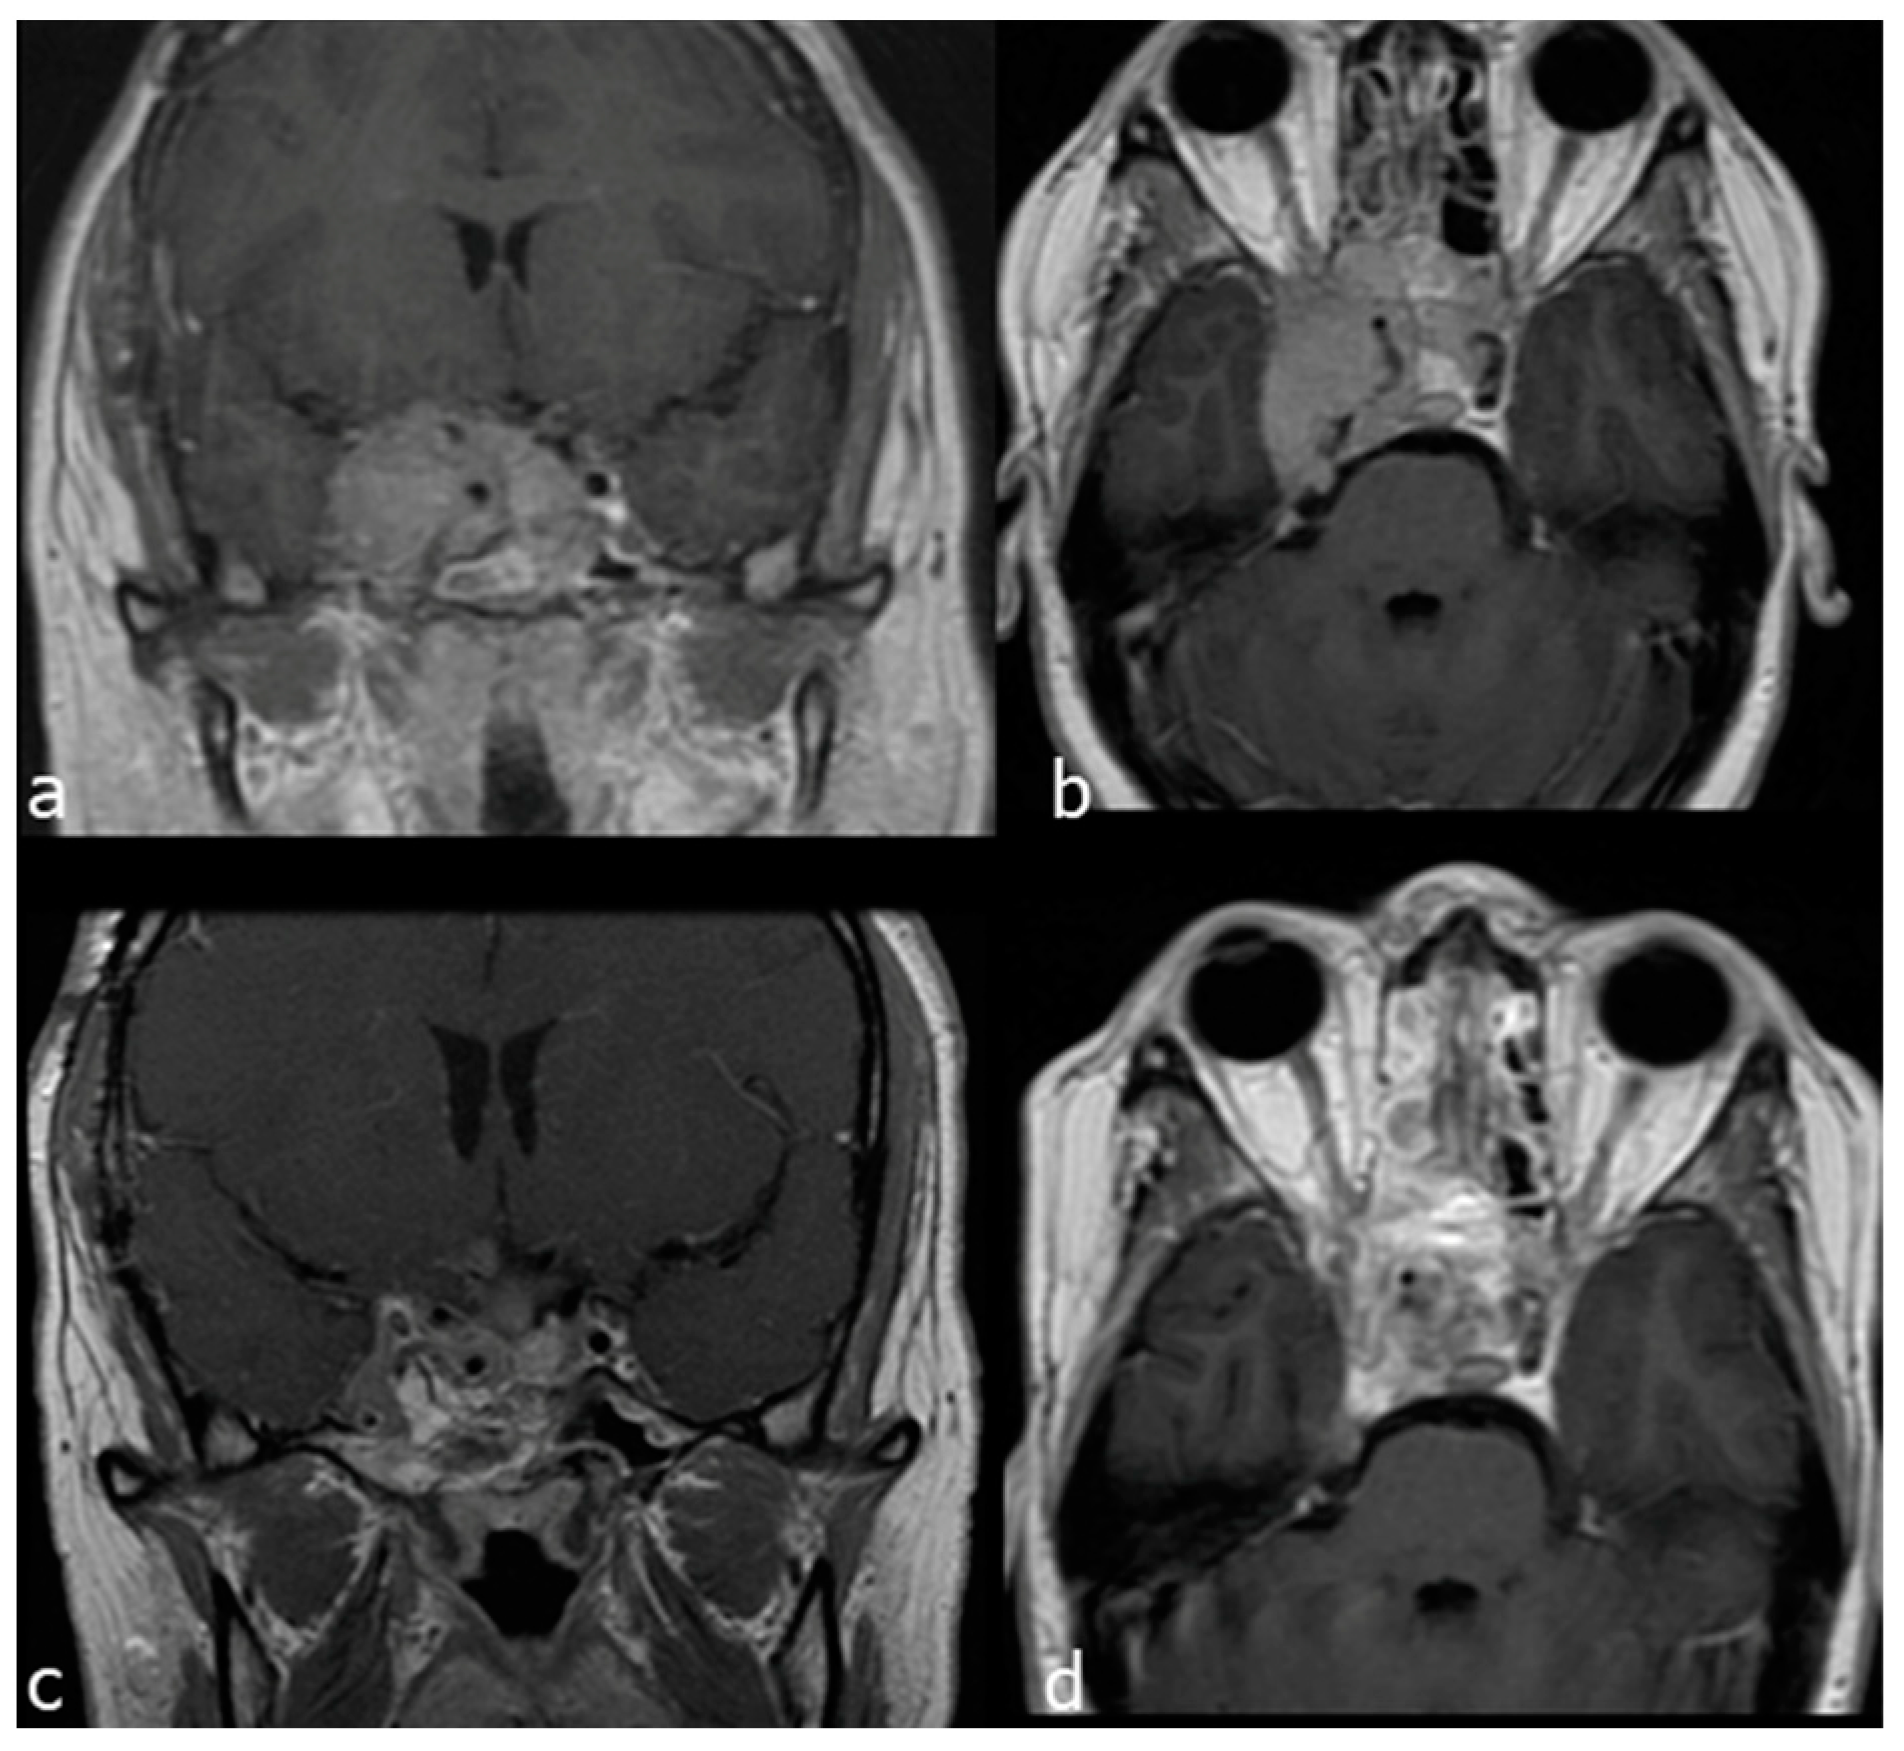

3.2. Surgical Series

- Case 1

- Case 2

- Case 3